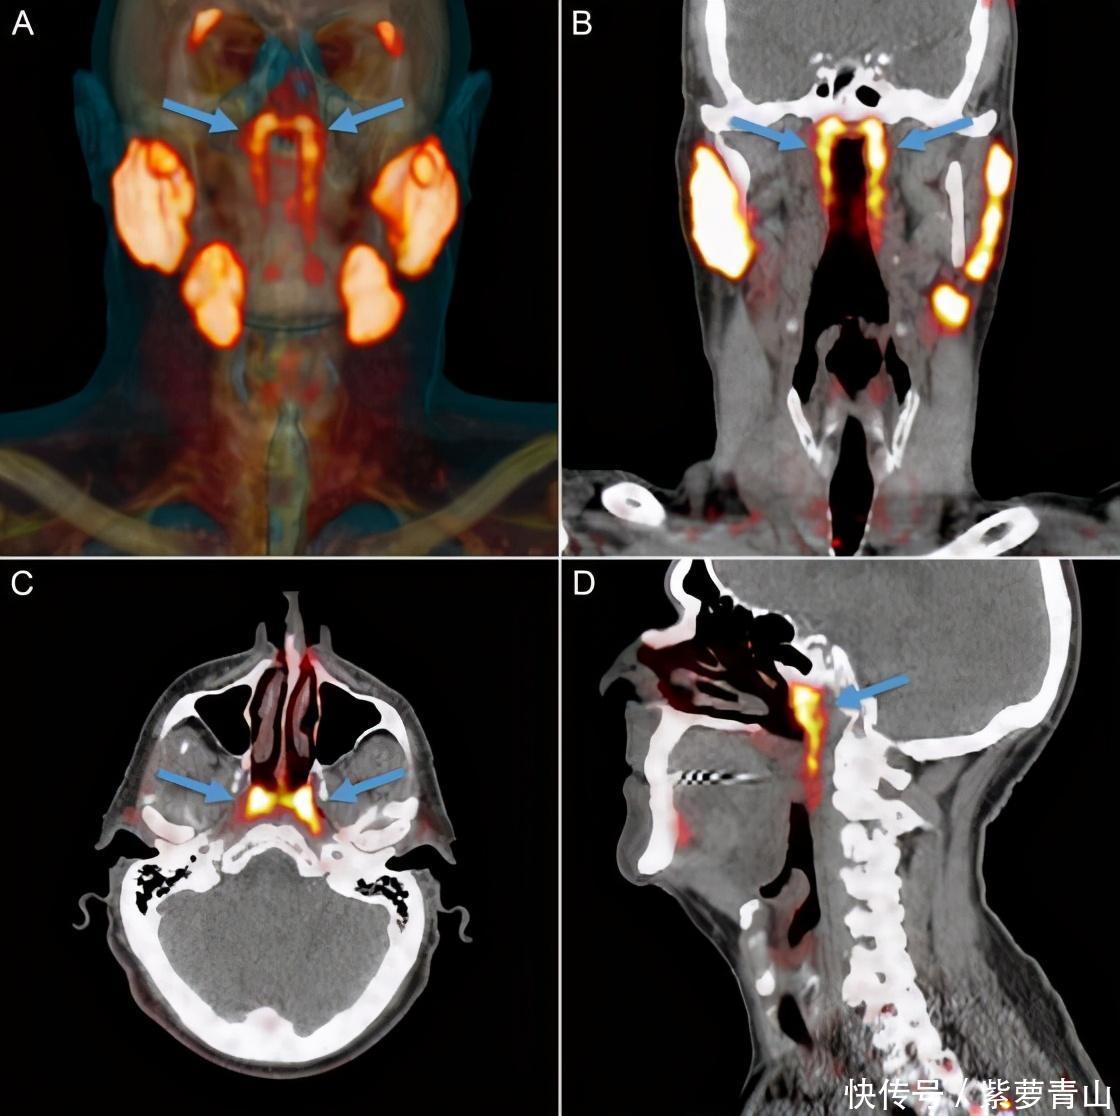

荷兰研究人员通过对前列腺癌症患者进行PSMA PET-CT扫描,PSMA是一种理想的前列腺癌诊断标志物。近年来,国际上最新的靶向PSMA核素分子影像检查(PSMA-PET/CT)在前列腺癌的精准治疗中发挥了越来越重要的作用。它可以有效显示出唾液腺。

他们将用放射性同位素标记的葡萄糖注入人体,以判断是否存在肿瘤。结果却在成像中发现了两个明亮区域,经过鉴定后他们认为这是唾液腺,但这些区域并没有已知的唾液腺。研究人员随后又调查了100个PSMA PET-CT扫描结果,并进行了两次有针对性的尸检,以确定这些腺体是否同样存在。

结果证明,在这块区域,的确存在一对未知的腺体,是由由黏液腺组织和流入鼻咽部的导管构成。所以研究人员断定存在第四种唾液腺,根据这组腺体所处的位置,研究人员将其命名为“咽鼓管腺”(tubarial glands),因为腺体十分靠近咽鼓管圆枕(torus tubarius),正是因为这对唾液腺隐藏在头骨底部,所以这数百年来,一直没有被人们发现。